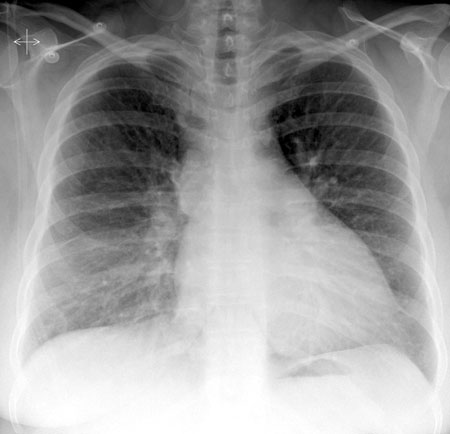

Radiografía de tórax normal.

Nota: Las imágenes se muestra para fines ilustrativos. No trate de sacar conclusiones comparando esta imagen con otras en el sitio. Solamente los radiólogos calificados deben interpretar las imágenes.